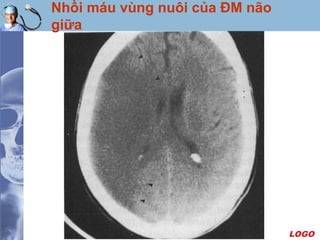

Nhồi máu vùng nuôi của ĐM não

giữa